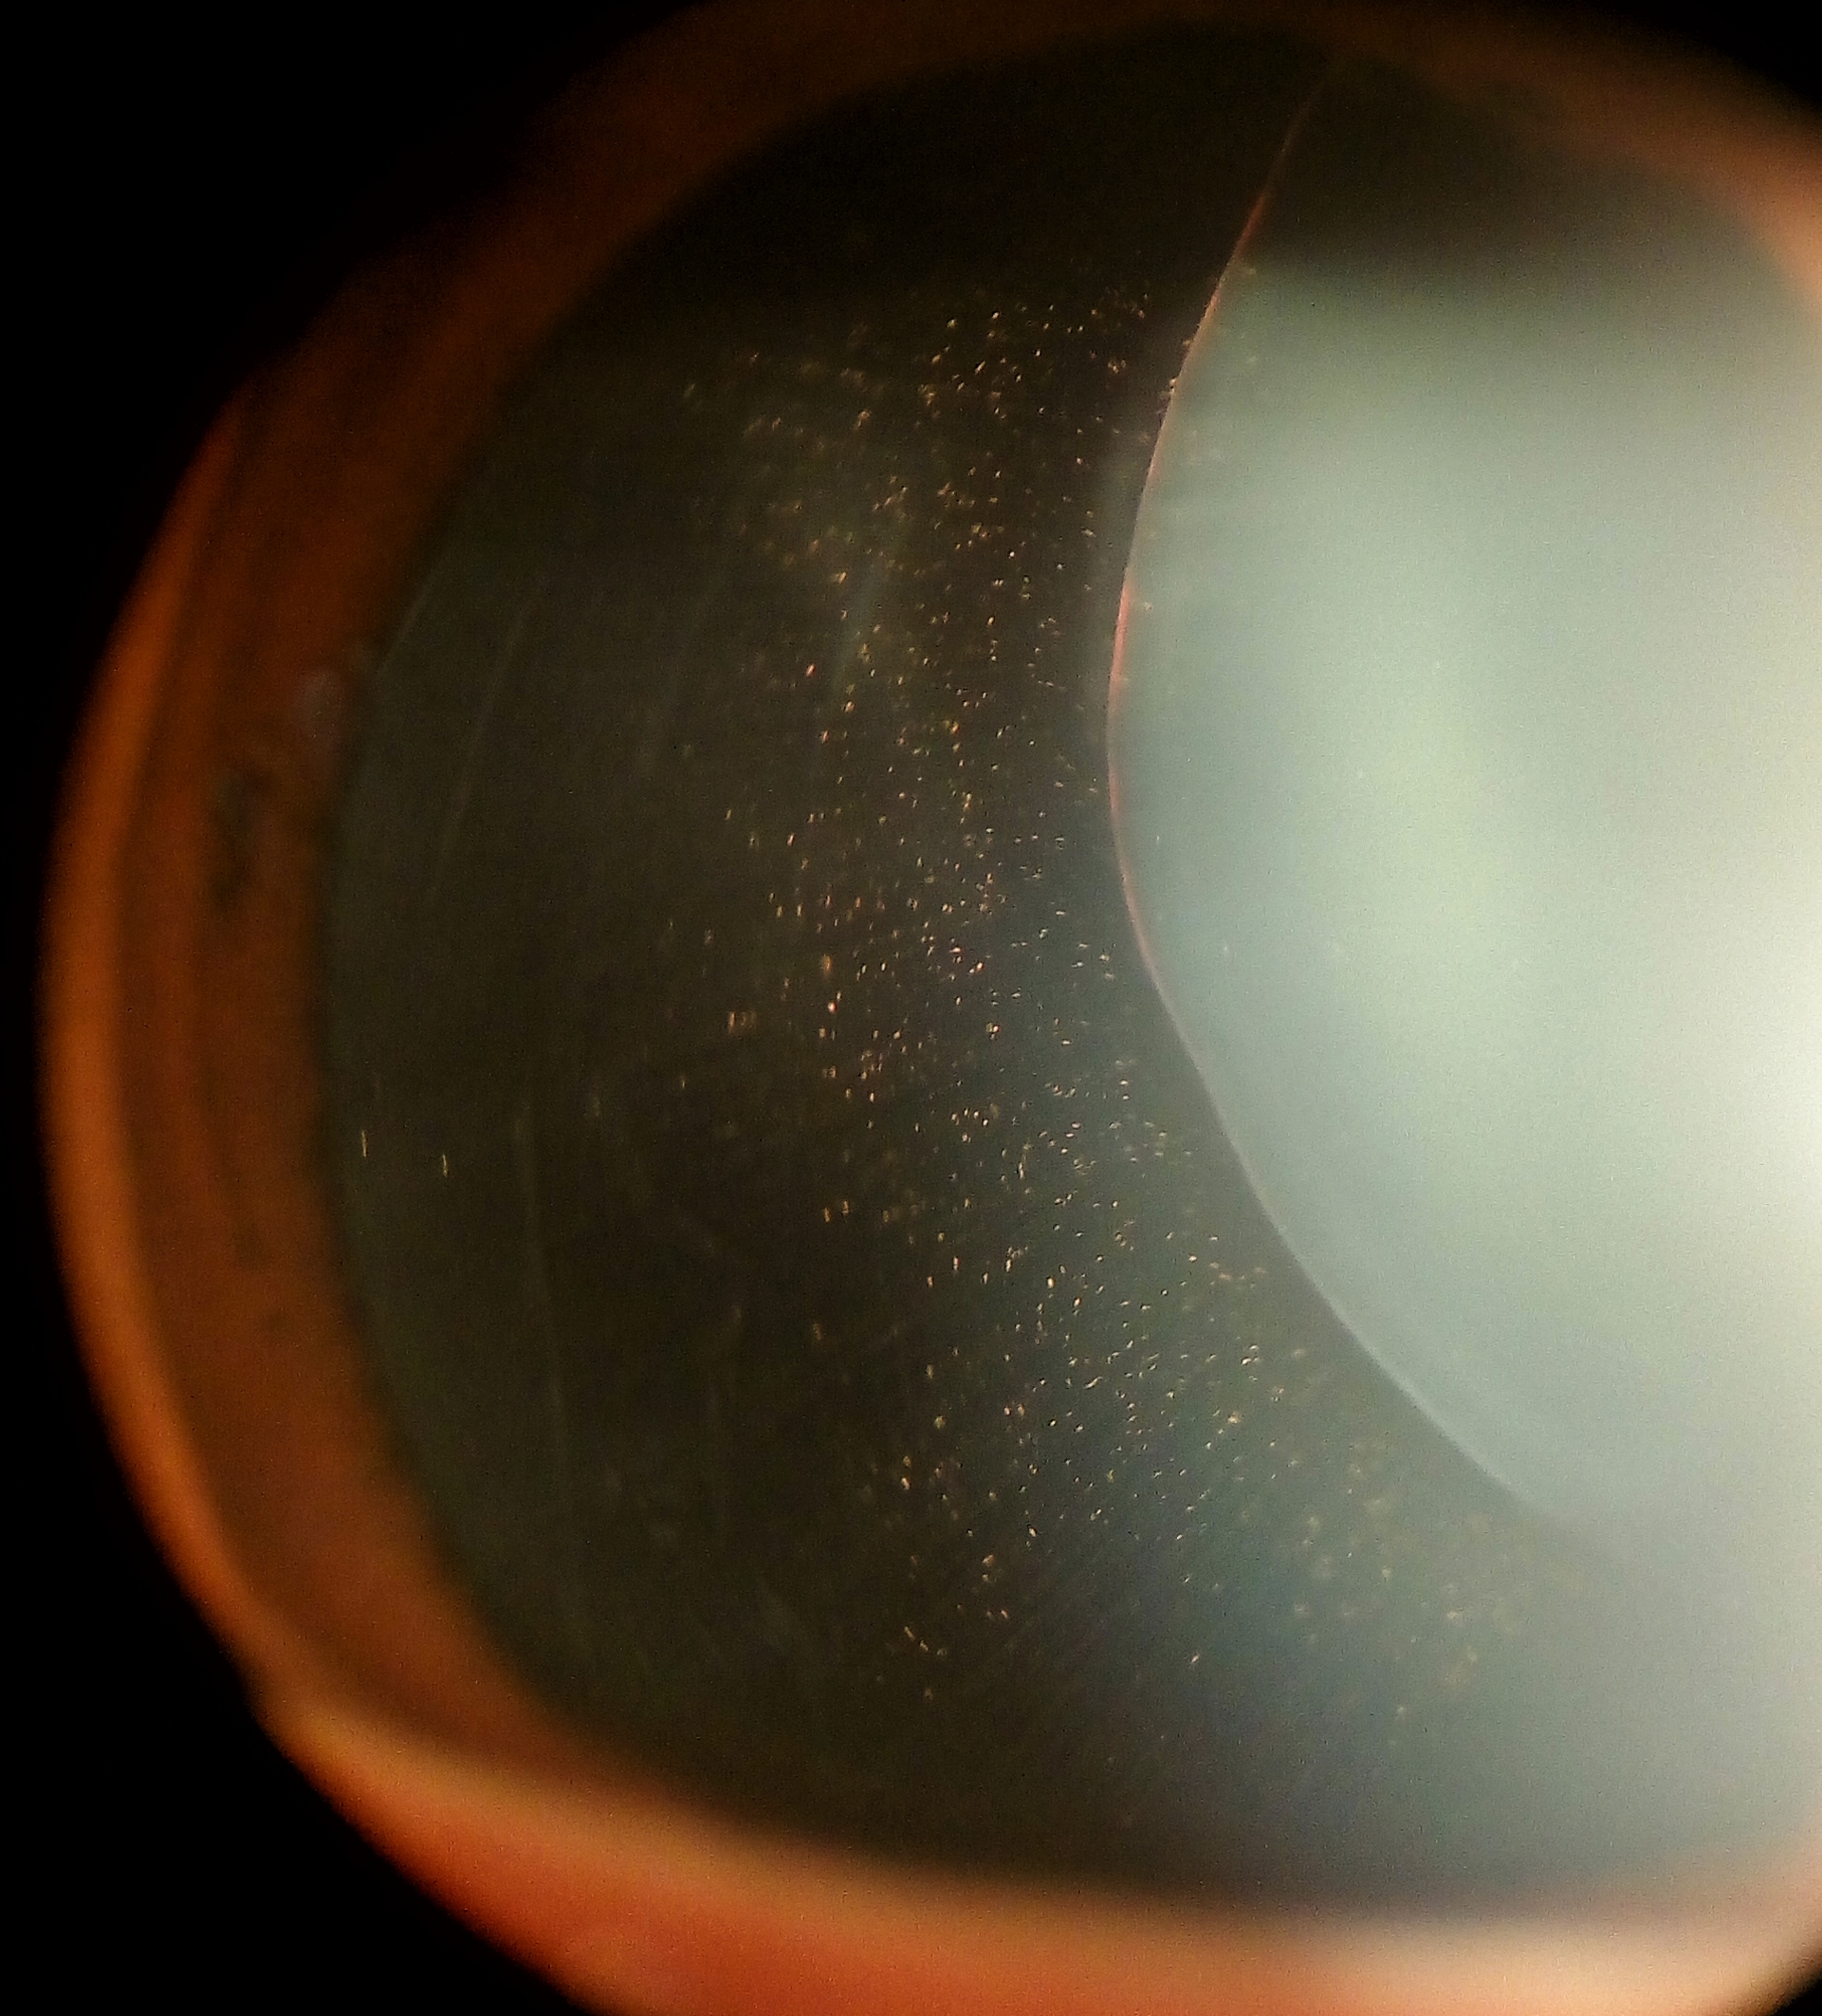

안과적인 특징은 공모양소수정체(spherophakia)입니다.

즉, 수정체가 찐빵과 같은 모양으로 넙데데하게 생깃것이아니라,

공모양으로 둥굴게 생겼습니다.

즉, 수정체 지름은 감소되어있고, 두께는 증가되어 있어

동공을 산동시켜보면 수정체의 전체 모양이 완전히 관찰가능합니다.

이 공모양 수정체가 탈구를 일으켜 동공과 맞닿는 경우,

2차적인 동공폐쇄 녹내장을 일으킬수 있습니다.